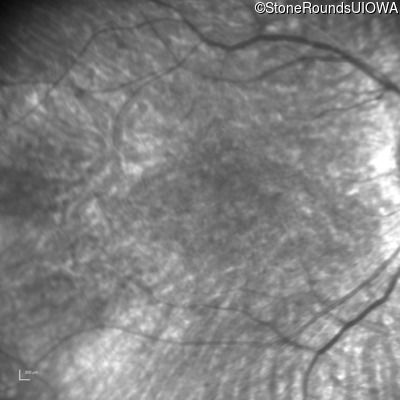

Age at visit: 10 years

Age at visit: 13 years